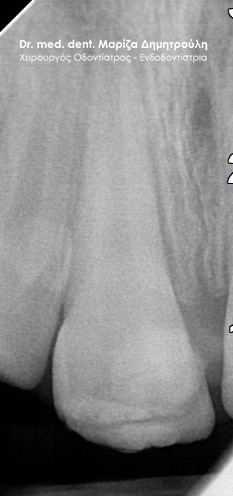

Ο ασθενής επισκέφτηκε το ιατρείο, γιατί πονούσε στον πάνω δεξί κεντρικό τομέα την τελευταία εβδομάδα. Στο δόντι είχε πραγματοποιηθεί απονεύρωση πριν 4 χρόνια. Επιθυμία του ήταν η διατήρηση του δοντιού στο στόμα. Η οδοντίατρος που είχε πραγματοποιήσει την απονεύρωση πριν χρόνια, του πρότεινε εξαγωγή του δοντιού και τοποθέτηση εμφυτεύματος.

Κλινικά η περιοχή γύρω από τον κεντρικό τομέα ήταν πρησμένη και εξερχόταν πύον από την ουλοδοντική σχισμή. Το δόντι είχε στεφάνη .Ο ασθενής με δική του πρωτοβουλία είχε ξεκινήσει τη λήψη αντιβίωσης.

Μετά τον ακτινογραφικό έλεγχο διαπιστώθηκε οτι η παλιά απονεύρωση ήταν ελλιπής/ ατελής στο άκρο της ρίζας του δοντιού.

Μετά απο συνεννόηση με τον ασθενή αποφασίστηκε να γίνει μία προσπάθεια διατήρησης της στεφάνης του δοντιού και παράλληλα να πραγματοποιηθεί επανάληψη της απονεύρωσης του δοντιού.

Μετά την χορήγηση τοπικής αναισθησίας τοποθετήθηκε ελαστικός απομονωτήρας (λάστιχο) και έγινε διάνοιξη του δοντιού μέσω της στεφάνης. Στη στεφάνη δημιουργήθηκε γλωσσικά μία τρύπα ώστε να διατηρηθεί η θήκη του δοντιού, ενώ ταυτόχρονα να είναι δυνατή η αφαίρεση του παλιού εμφρακτικού υλικού στη ρίζα του δοντιού. Στη συνέχεια ξεκίνησε η επανάληψη της ενδοδοντικής θεραπείας (απονεύρωση) με την αφαίρεση του παλιού εμφρακτικού υλικού σε όλο το μήκος της ρίζας του δοντιού. Ακολούθησε η επεξεργασία του δοντιού με μηχανοκίνητα εργαλεία και οι διακλυσμοί ( έκπλυση ) στο εσωτερικό της ρίζας για την απομάκρυνση των νεκρών οδοντικών ιστών / κυττάρων και την απολύμανση της ρίζας. Έγινε τοποθέτηση φαρμάκου και έγινε προγραμματισμός για τη συνέχιση της απονεύρωσης σε επόμενο ραντεβού.

Εφόσον ο ασθενής δεν πονούσε, το οίδημα στην περιοχή είχε υποχωρήσει και το δόντι ήταν ασυμπτωματικό ακολούθησε η ολοκλήρωση της απονεύρωσης με την έμφραξη της ρίζας του δοντιού.

Το σημείο της στεφάνης που τροχίστηκε γλωσσικά έκλεισε με σφράγισμα σύνθετης ρητίνης. Αυτή ήταν μία συμβιβαστική λύση σε συνεννόηση με τον ασθενή, προκειμένου το δόντι να παραμείνει στο στόμα και να μην εξαχθεί.

ΠΡΙΝ

ΜΕΤΑ